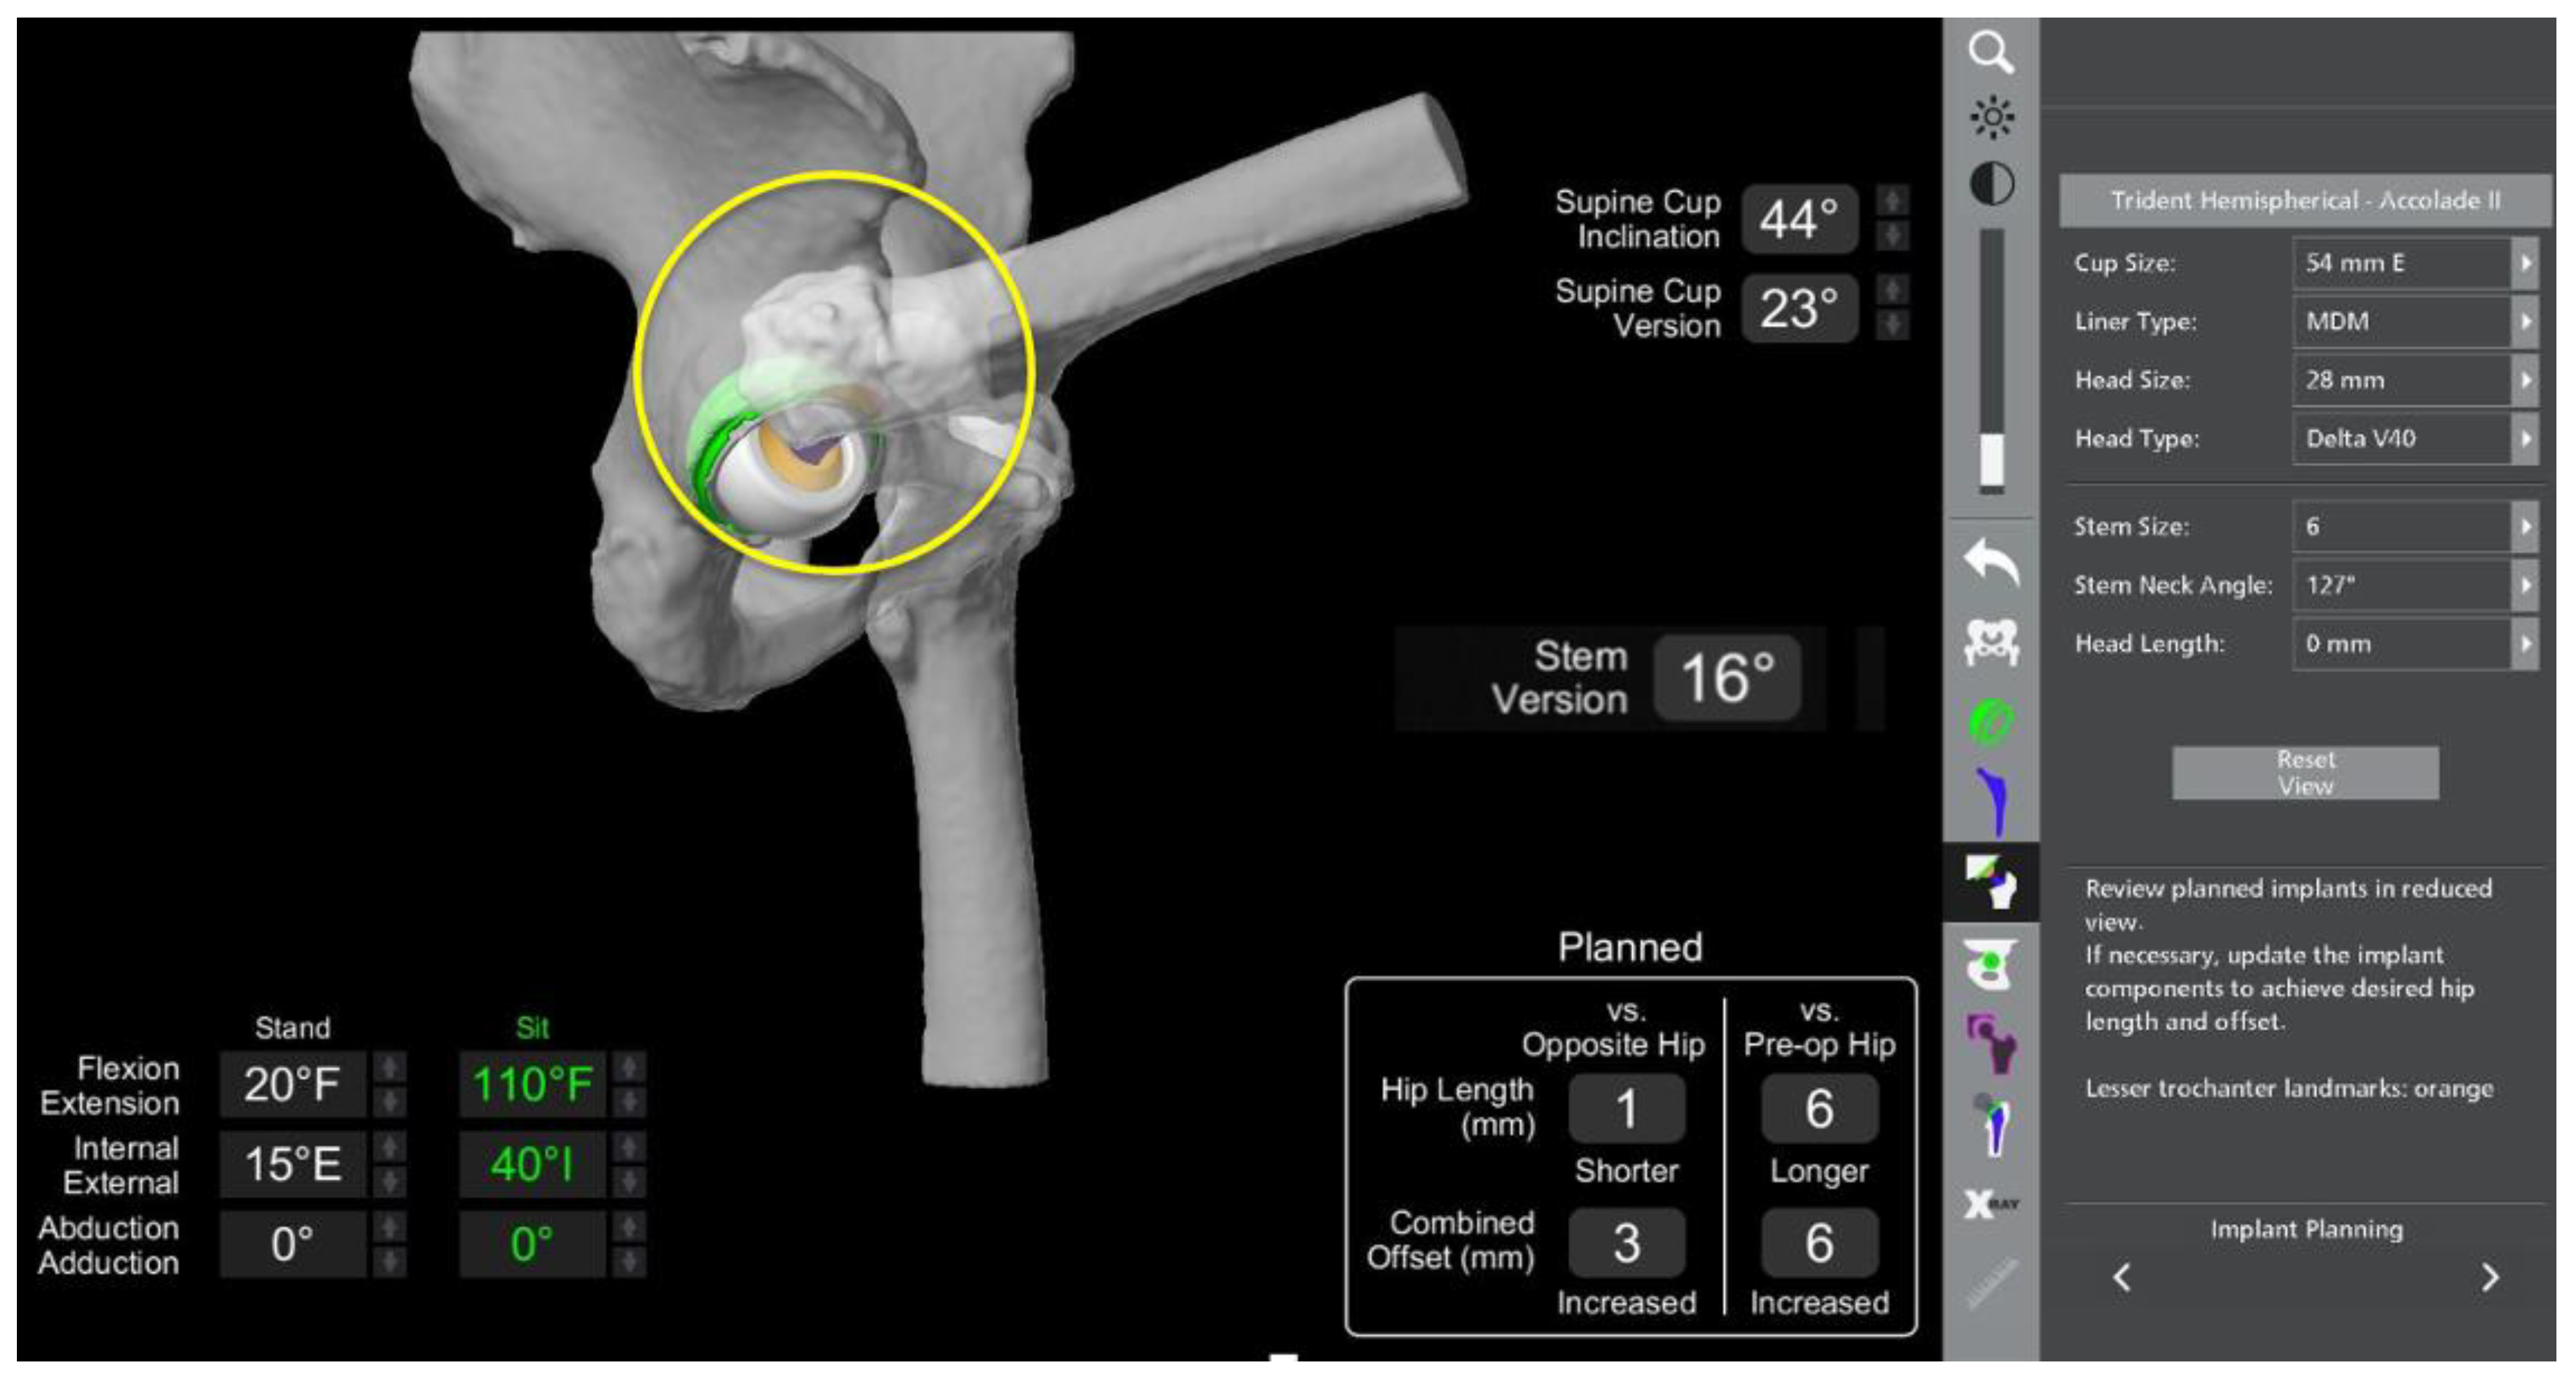

- In this case, the native femoral retroversion (−6 degrees) posed a challenge in avoiding impingement (Figure 7). Upon assessing VROM, bone-on-bone and implant-on-implant impingement in deep flexion were noted (Figure 8). Using the robotic software, the planned femoral version was corrected to +16 in the femoral broach (Figure 9a,b).

- The robotic software also enables preoperative and intraoperative visualisation of the anticipated postoperative X-rays accounting for any changes to the plan. In addition, the software allows for calculation of changes to the leg length offset compared to the preoperative and contralateral hips. In this case, the leg length was 1 mm longer compared to the opposite hip, and the combined offset was 6 mm increased compared to that preoperatively (Figure 12a,b).